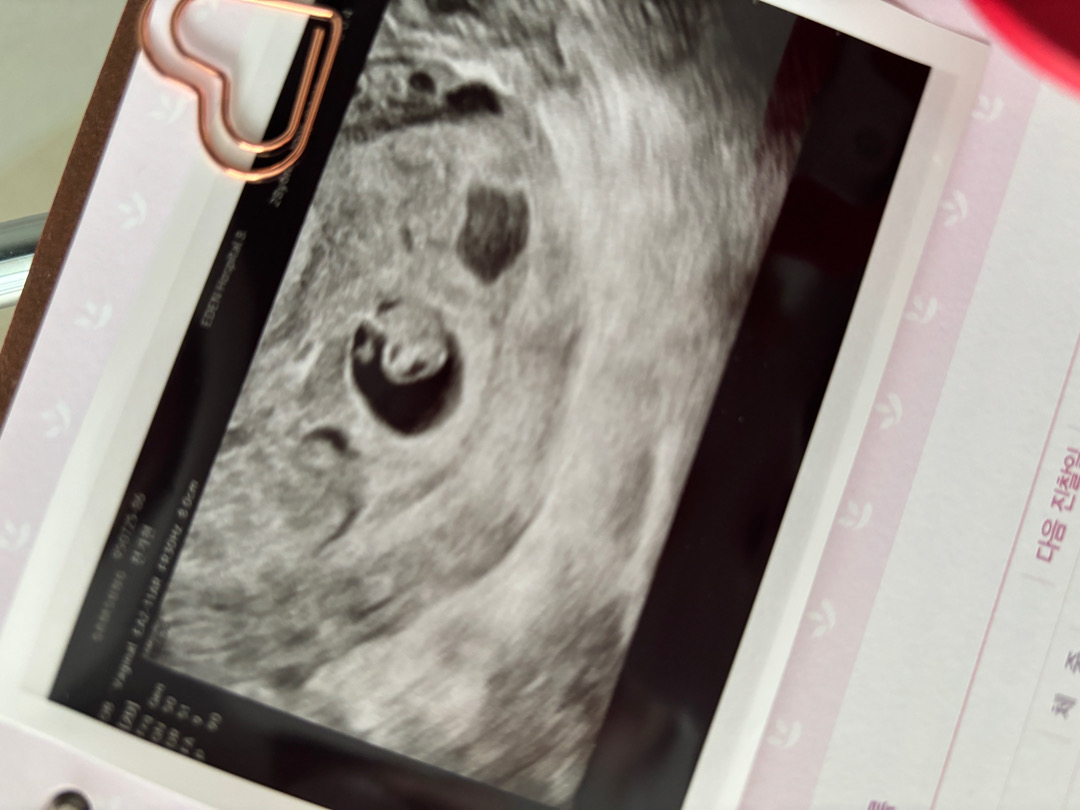

두번째 검진 받고왔어요🧸

12/9 막생으로 딱! 5주차때 첫검진가서 5주 3일이라고 하셨는데 2주지난 오늘 7주차일줄 알고 병원갔는데 6주 3일로.. 줄었더라구요.. 심장소리도 듣고왔지만 임신하고 괜시리 생각도 많고 걱정도 많아서 괜하 아가가 조금씩 크고있는걸까요 ㅠㅠ.. 피고임이랑 심장이 아직은 천천히 뛴다구.. 증상이 없어서 괜히 아가가 잘있는지 너무 걱정했나봐요😂 다른분들도 초진보다 예정일이 이롷게 늦어지는 경우도 있나요??